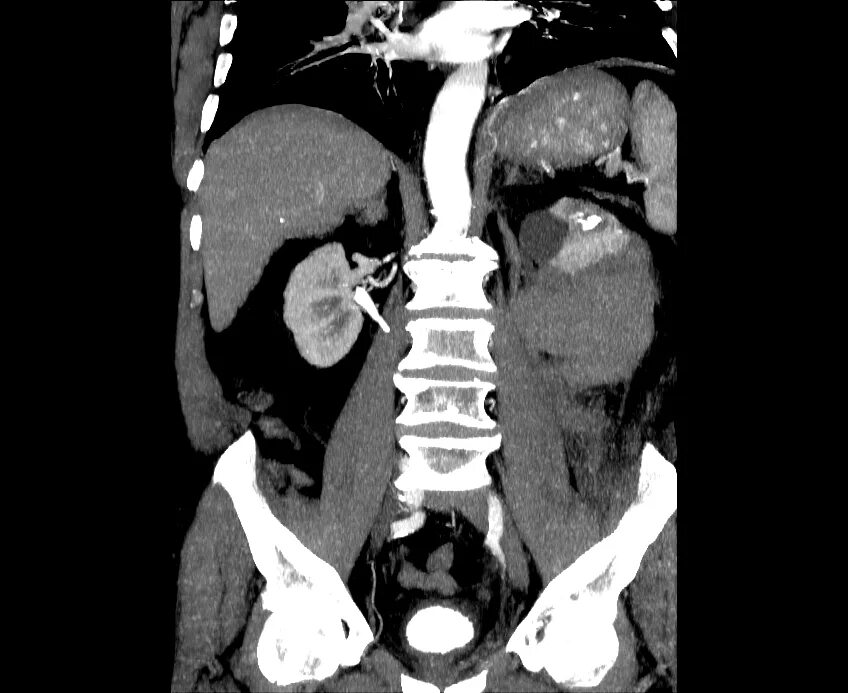

Кальциноз брюшного отдела